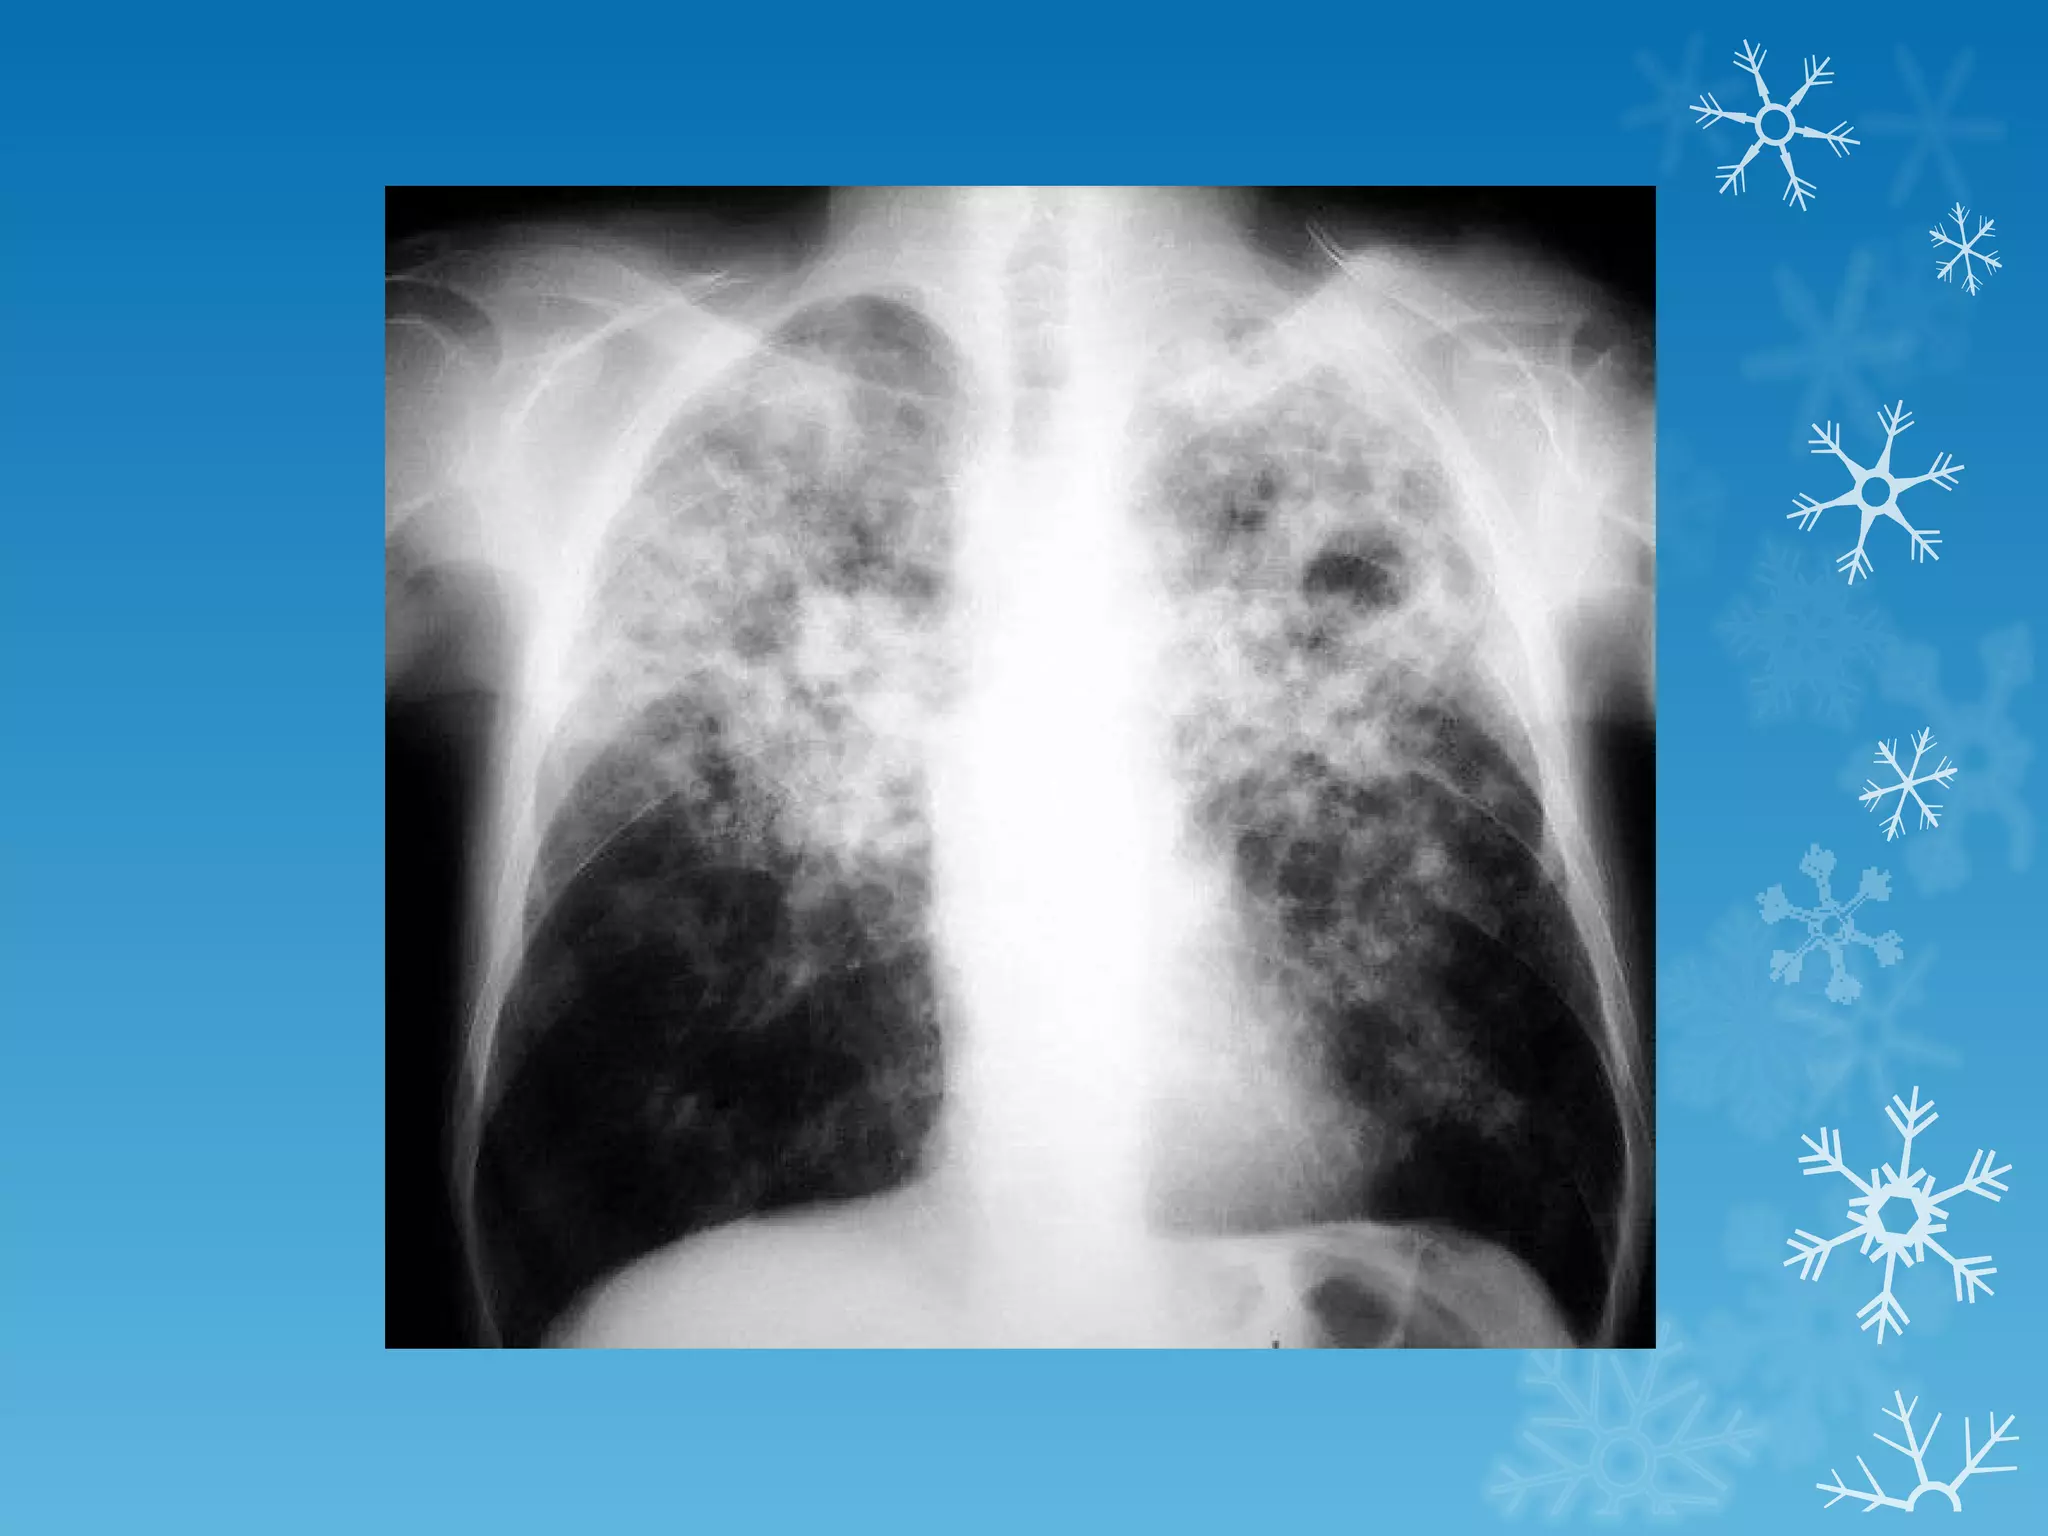

This document discusses chest x-ray interpretation and provides guidance on evaluating x-rays. It explains that tissue density determines how an x-ray beam penetrates, with denser tissues appearing whiter and less dense tissues appearing blacker. It also outlines different chest x-ray views and factors to consider like patient orientation, age, gender, and rotation. Abnormalities are described as appearing too white, too black, too large, or in the wrong place. The document stresses a systematic approach of identifying, localizing, describing lesions, and providing differential diagnoses.